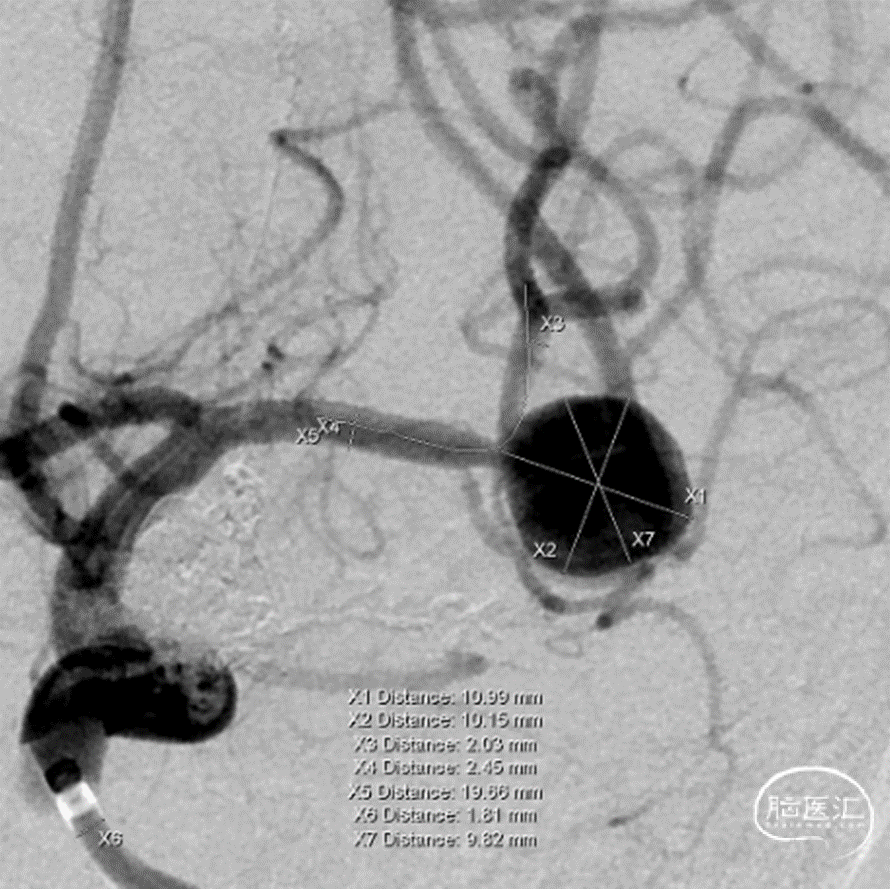

治疗经过